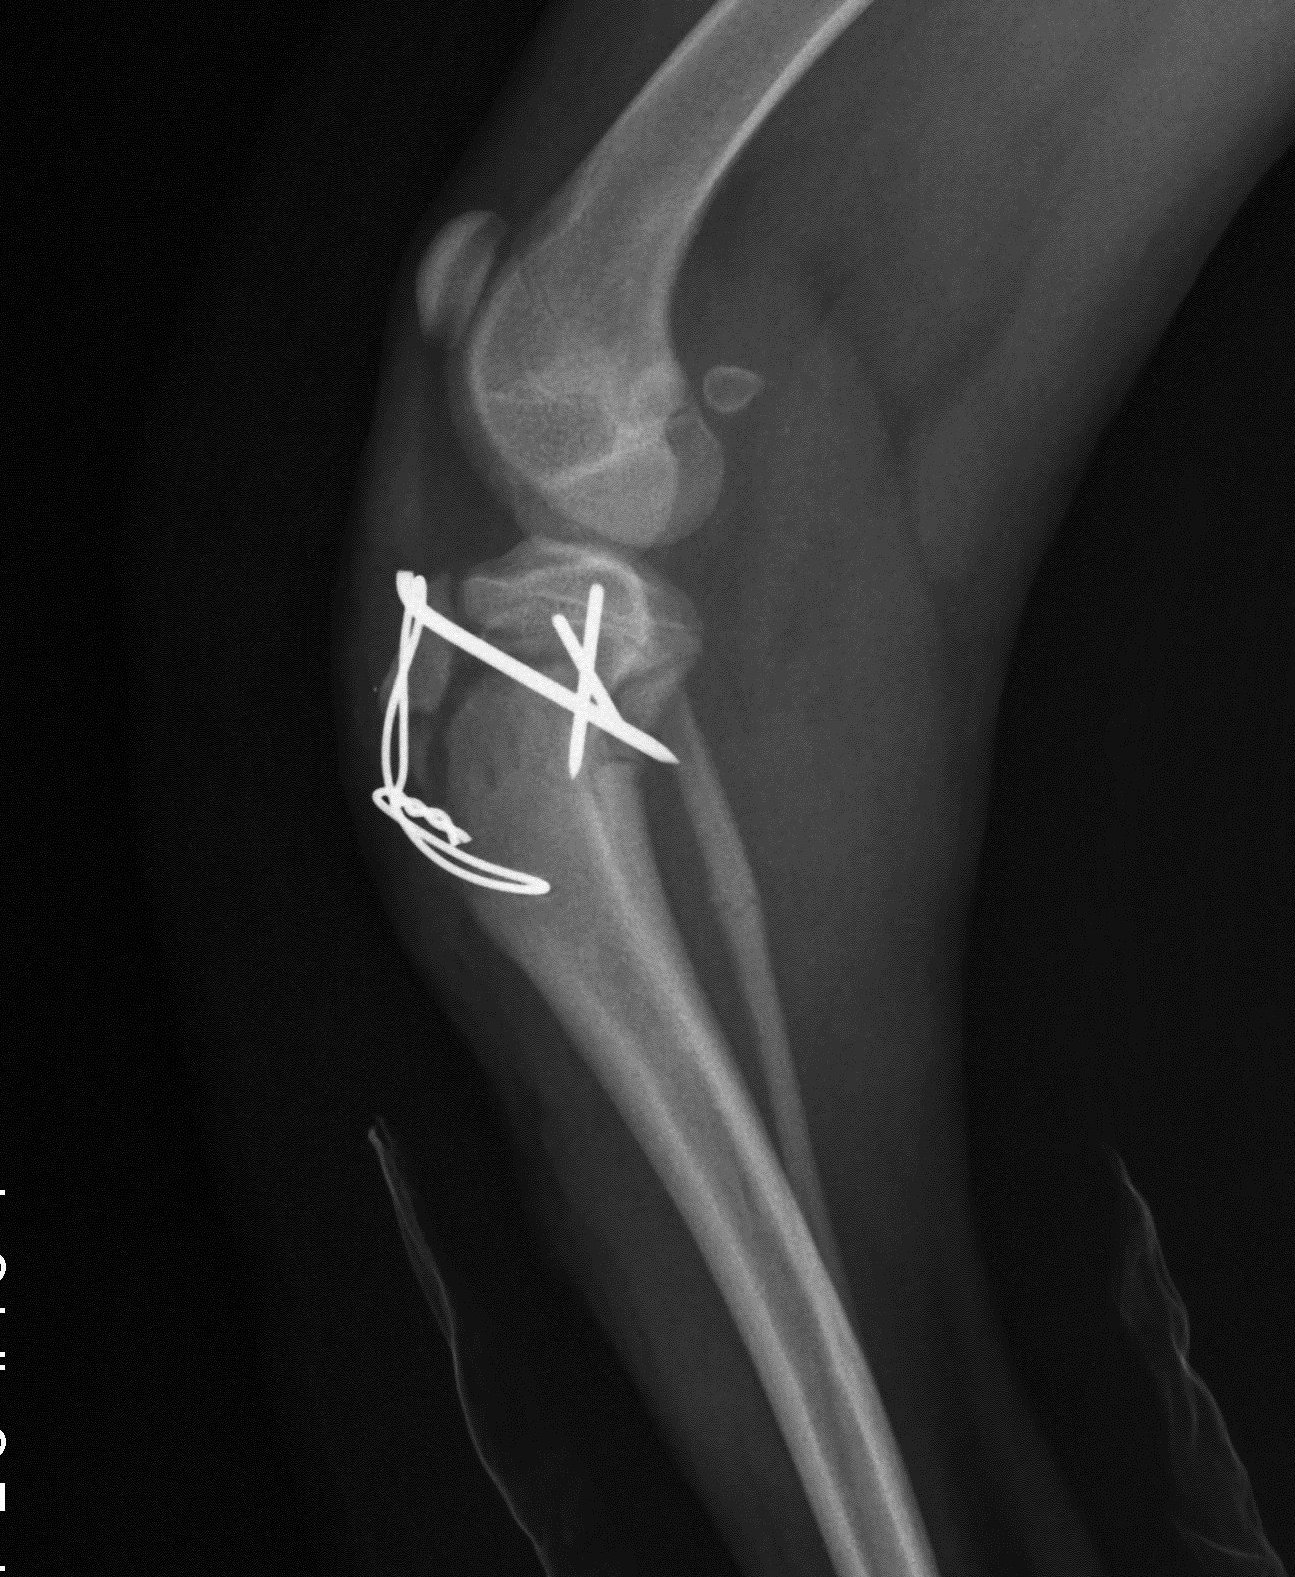

Descrizione della frattura di rotula,trattamento e complicanze di una tra le piu' frequenti fratture trattata sia con intervento chirurgico che con applicazione di la dinamica ,che spiega la frattura della rotula, avviene per caduta con il ginocchio flesso a cui segue una contrazione repentina del quadricipite per. Se la rotula è frammentato in diversi pezzi, allora avrete bisogno di un intervento chirurgico. Le fratture della rotula possono essere causate da forze indirette o da un trauma. Una frattura della rotula spesso comporta una lesione cutanea, l'insorgenza di gonfiore e un significativo tuttavia queste lesioni verranno trattate in un secondo momento essendo la guarigione della dopo la guarigione è necessario definire un percorso riabilitativo che abbia come obiettivo il. Salve, tre giorni fa mi sono procurato una frattura articolare composta al 1°dito piede del piede destro giocando a calcetto, vorrei sapere i tempi di guarigione. Gli ho chiesto se potrò tornare a fare ciò che facevo prima e lui dice che. Ciao come e andato il decorso della frattura? Mehmet erdogan ci spiega le differenti guarigioni post intervento della zona donatrice e della zona ricevente. In ogni caso la terapia riabilitativa giocherà un ruolo fondamentale per ottenere il pieno. Si eseguono delle sedute di fisioterapia, che si basano sull'esecuzione di esercizi di. Tempi di guarigione frattura vertebrale. Quest'ultima serve ad eliminare la rigidità e a far riacquistare la forza muscolare. Le rime di frattura verticali, con tempi di recupero che possono variare. Tempo di guarigione per una caviglia fratturata può dipendere da numerosi fattori. Se hai rotto solo l'osso ma legamenti e balle varie sono rimasti illesi vedrai che. La frattura di rotula rappresenta circa l'1% di tutte le fratture, sia negli adulti che nei bambini. La frattura quinto metatarso è per definizione la rottura traumatica o non traumatica della base prossimale del quinto metatarso del piede.